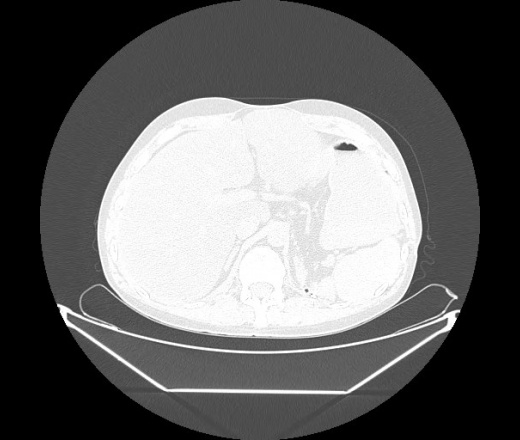

М. 1984 г.р.  Лихорадка 39, кашель , одышка.. и надоевший всем вопрос- "типично ли для ковид?" ( в настоящее время на него обязательно нужно дать ответ в своем протоколе)

На мой взгляд нетипично для ковид: много центрально-расположенных поражений, лобарное поражение нижней доли слева. 50/50

Не типичая картина для ковид.

КТ-признаки двусторонней бактериальной пневмонии.

Все верно, здесь абсолютно нетипичная картина, несмотря на матовое стекло с ретикулярными изменениями, но почему-то  посчитали иначе. Кстати,  "малыша" не заметили)?

Добавил 6 день

да, это я о абсцессе.